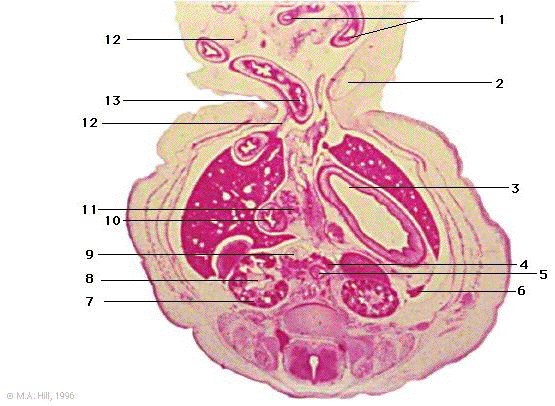

1 |

intestinal herniation |

2 |

umbilical vein |

3 |

stomach body |

4 |

coeliac ganglion |

5 |

aorta |

6 |

spleen |

7 |

metanephrogenic capsule derivatives |

8 |

ureteric bud derivatives (metanephros) |

9 |

inferior vena cava |

10 |

duodenum |

11 |

pancreas |

12 |

mesentery |

13 |

returning limb of midgut loop |